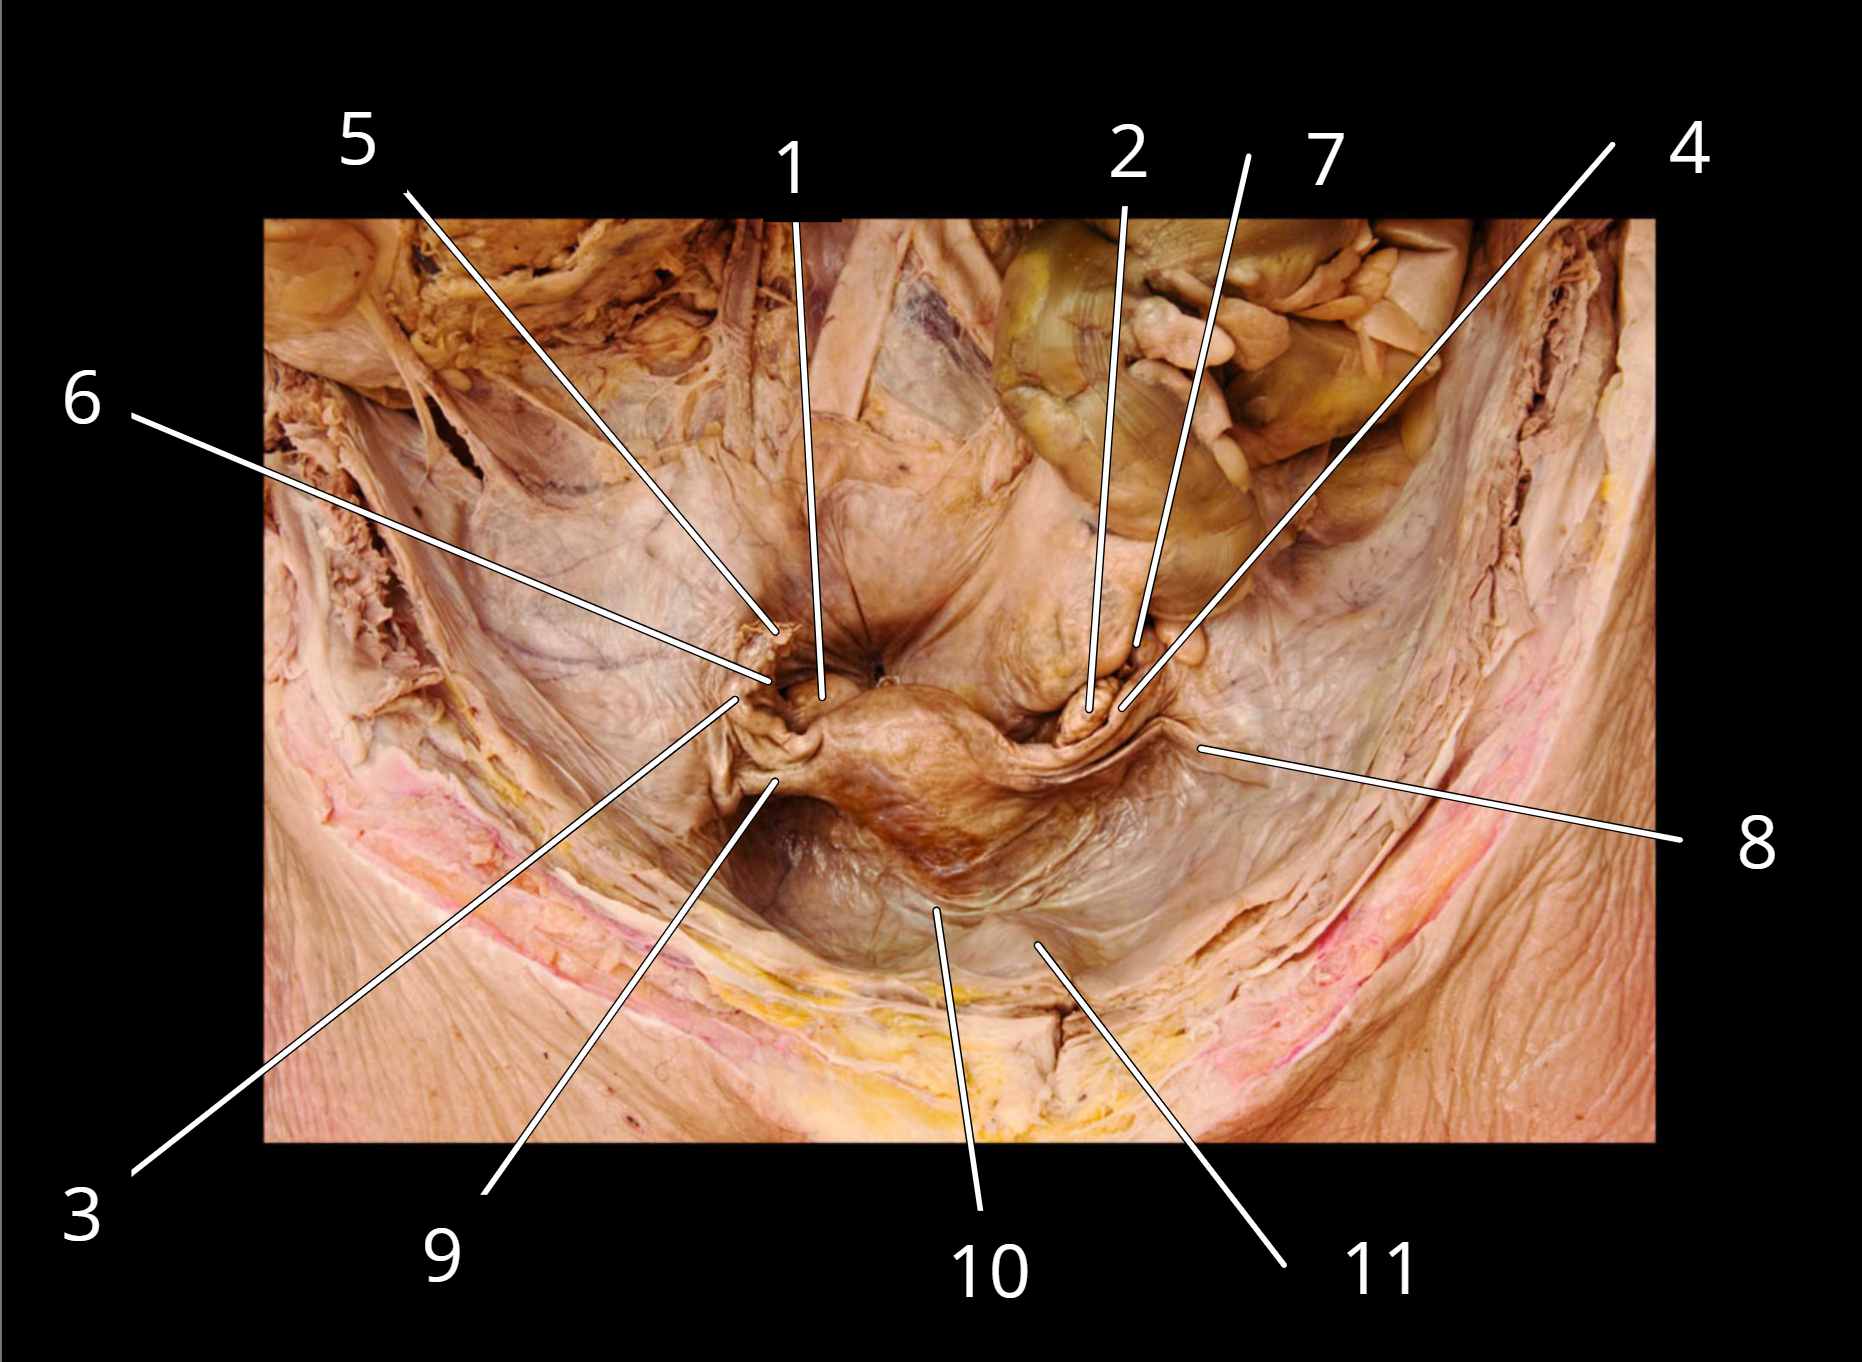

Uterus

1. Right ovary

2. Left ovary

3. Right uterine tube

4. Left uterine tube

5. Fimbriae of right uterine tube

6. Right ovarian ligament

7. Left ovarian ligament

8. Left round ligament

9. Right round ligament

10. Broad ligament

11. Urinary bladder